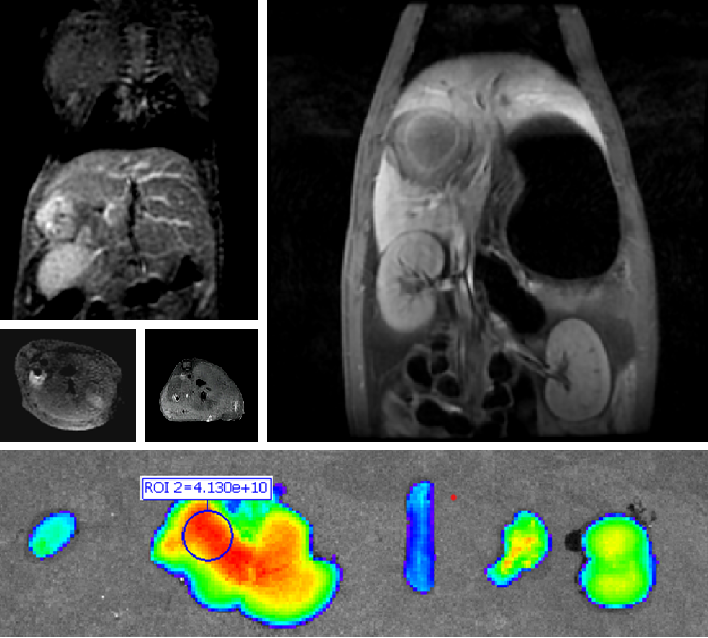

创新双模态造影剂(PL002)

普利制药自主研发的双模态造影剂PL002,已经获得美国FDA临床试验批件。PL002的研制首次提出通过整合磁共振技术,弥补现有荧光染料假阳性率高、透射深度有限等的短板,进而提升手术的精确性,降低手术过程中的风险,是全球首个获批临床试验的荧光/磁共振双模态造影剂。本项目预示着海南普利在造影剂领域的长期投入,并致力于开展独具特色的差异化国际化创新发展路径。